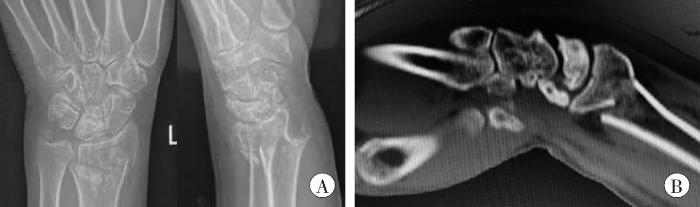

某年11月29日(受伤当日)当地人民医院X线片(图1A)示:左桡骨远端骨质中断,断端移位并成角,骨折远端向桡侧、背侧移位,近端向掌侧移位,尺骨茎突撕脱骨折。左手舟骨及月骨形态均欠规整。周围软组织区肿胀。

图1

受伤当日影像学检查结果

A:X线片;B:CT片。

Fig. 1

Imaging examination results on the day of injury

某年11月29日(受伤当日)当地人民医院CT片(图1B)示:左桡骨远端及尺骨茎突骨质中断,桡骨断端错位,周围软组织肿胀。左腕月骨骨折线累及关节面、边缘骨质硬化、有囊变,月骨与腕骨关节面塌陷,月骨与桡骨关节面未见明显塌陷;左手舟骨骨质欠规整,考虑左手舟骨及月骨陈旧性骨折并月骨无菌性坏死。